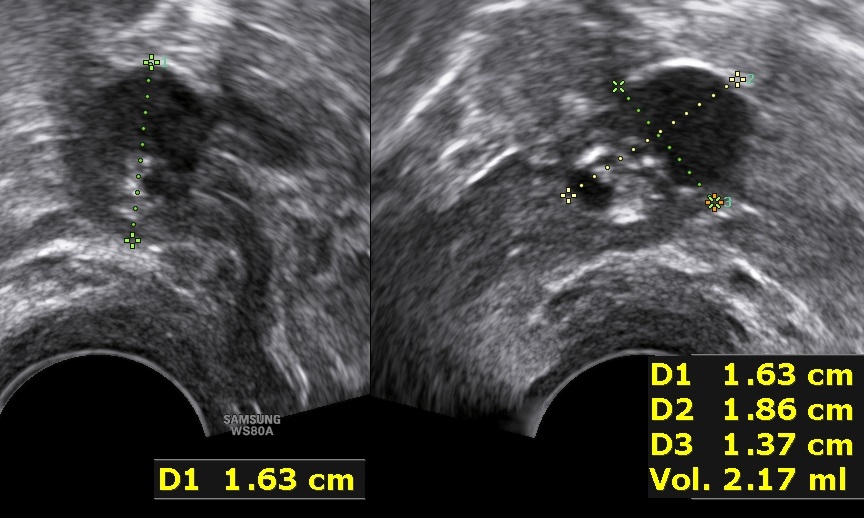

Instead, the presence of thin-walled, microcystic formations along the borders of the solid component (typically 1-3mm in size) is thought to be pathognomonic of borderline ovarian tumors (5).

A small borderline tumor with presence of microcystic formations.